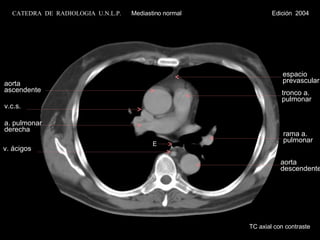

aorta ascendente v.c.s. a. pulmonar derecha espacio prevascular tronco a. pulmonar aorta descendente v. ácigos E rama a. pulmonar TC axial con contraste CATEDRA  DE  RADIOLOGIA  U.N.L.P.   Mediastino normal  Edición  2004

aorta ascendente v.c.s.a. pulmonar derecha espacio prevascular tronco a. pulmonar aorta descendente v. ácigos E rama a. pulmonar TC axial con contraste CATEDRA DE RADIOLOGIA U.N.L.P. Mediastino normal Edición 2004